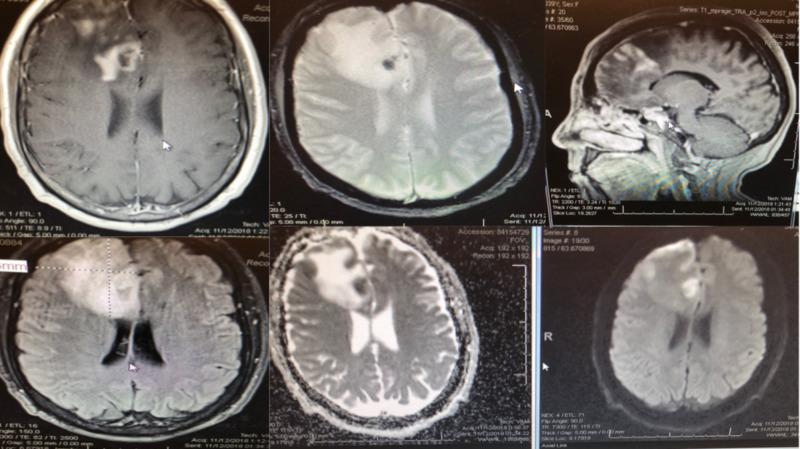

Primary angiitis of the central nervous system (PACNS) is a rare form of vasculitis and is confined entirely to the central nervous system (CNS)without systemic involvement. We report a rare case of PACNS in a 39-year-old female with new onset seizures and a right frontal enhancing mass. Initially the patient was thought to have a high-grade glioma and thus underwent a right frontal craniotomy for resection of right frontal mass. Intraoperatively, two fresh tissue samples were sent for intraoperative consultation. Sample 1 showed predominantly necrotic tissue and scant glial cells while sample 2 revealed glial tissue favoring gliosis versus low-grade neoplasm with necrosis and a few acute inflammatory cells. Final pathological diagnosis was consistent with PACNS. Postoperatively, the patient recovered well from surgery with no neurological deficits and was discharged on postoperative day 3. Two weeks after surgery the patient was started on cyclophosphamide and prednisone by Rheumatology. At one month follow up, the patient remained asymptomatic and seizure free.

中枢神经系统原发性血管炎(PACNS)是一种罕见的血管炎形式,完全局限于中枢神经系统(CNS),无全身受累。我们报告一例罕见的PACNS病例,患者为39岁女性,新发癫痫,右侧额叶有强化肿块。最初,该患者被认为患有高级别胶质瘤,因此接受了右侧额叶开颅手术以切除右侧额叶肿块。术中,送了两份新鲜组织样本进行术中会诊。样本1主要显示坏死组织和少量胶质细胞,而样本2显示胶质组织,倾向于胶质增生而非伴有坏死和少量急性炎症细胞的低级别肿瘤。最终病理诊断与PACNS一致。术后,患者手术恢复良好,无神经功能缺损,术后第3天出院。术后两周,风湿科开始让患者服用环磷酰胺和泼尼松。随访1个月时,患者无症状且无癫痫发作。